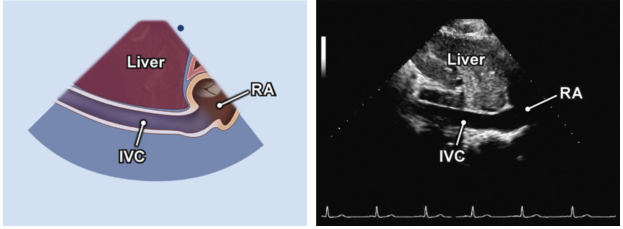

IVC我们选择在剑突下四腔心切面获得,如图4所示。

图4 剑突下四腔心下腔静脉切面